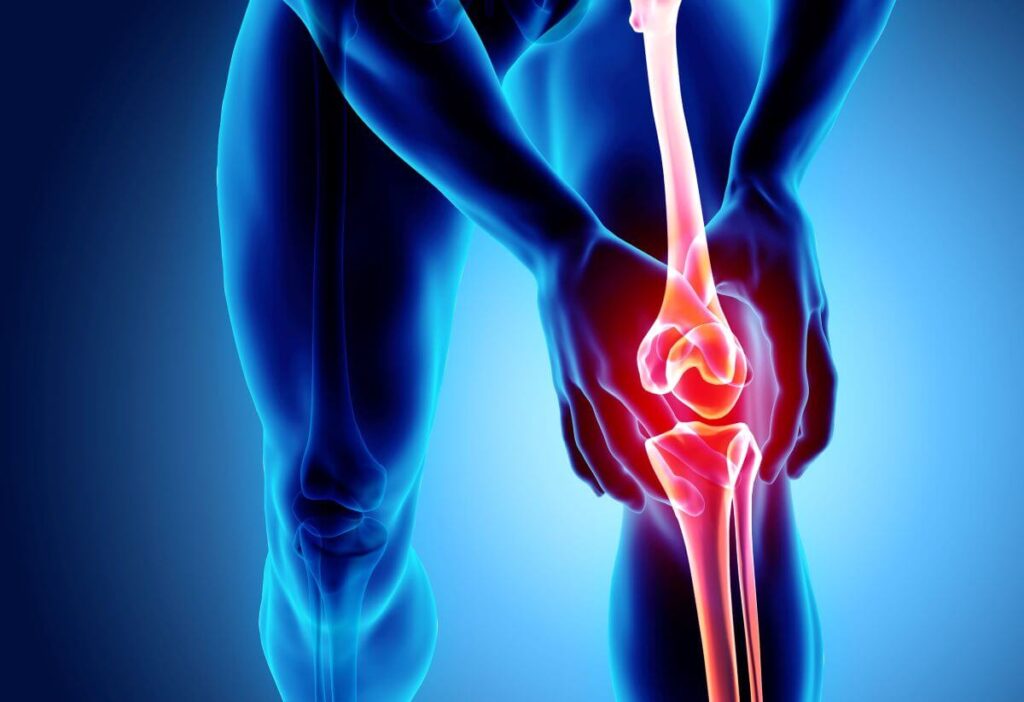

Todas las articulaciones y, en particular, las de las rodillas cuentan con un cartílago que es el tejido que conecta los huesos y actúa como amortiguador de los impactos sobre esa estructura ósea. Por la práctica de deportes extremos, enfermedades degenerativas o por envejecimiento, puede producirse desgaste en el cartílago de las rodillas y, en consecuencia, presentarse dolores articulares.

Además de dolor, las articulaciones de las rodillas pueden presentar inflamación, enrojecimiento y deformación. Todo ello como consecuencia de procesos degenerativos que suelen causar desgastes y daños en el cartílago articular difíciles de revertir. Lo importante es cuidar las articulaciones, prevenir hasta donde es posible los daños en el cartílago y tratar de fortalecer los huesos, los ligamentos y tendones.

Como hemos dicho, en la rodilla se encuentra el cartílago, que es un tejido flexible que recubre los huesos que forman la articulación. También están presentes los ligamentos cuya función es conectar los huesos para mantener la estabilidad, y los tendones que son flexibles, resistentes y conectan los huesos con los músculos.